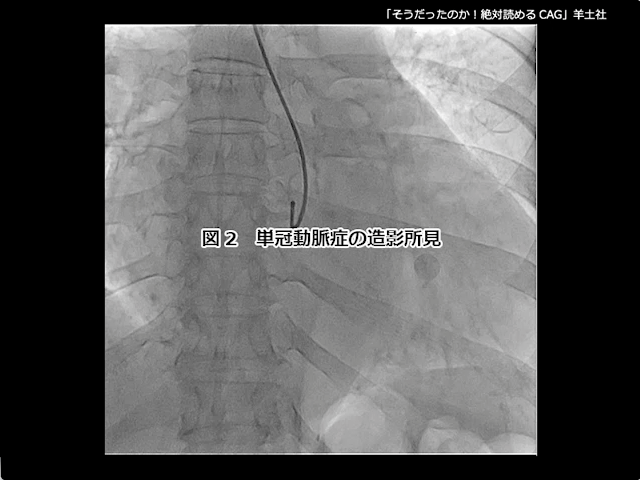

第5章-1 急性冠症候群の造影所見